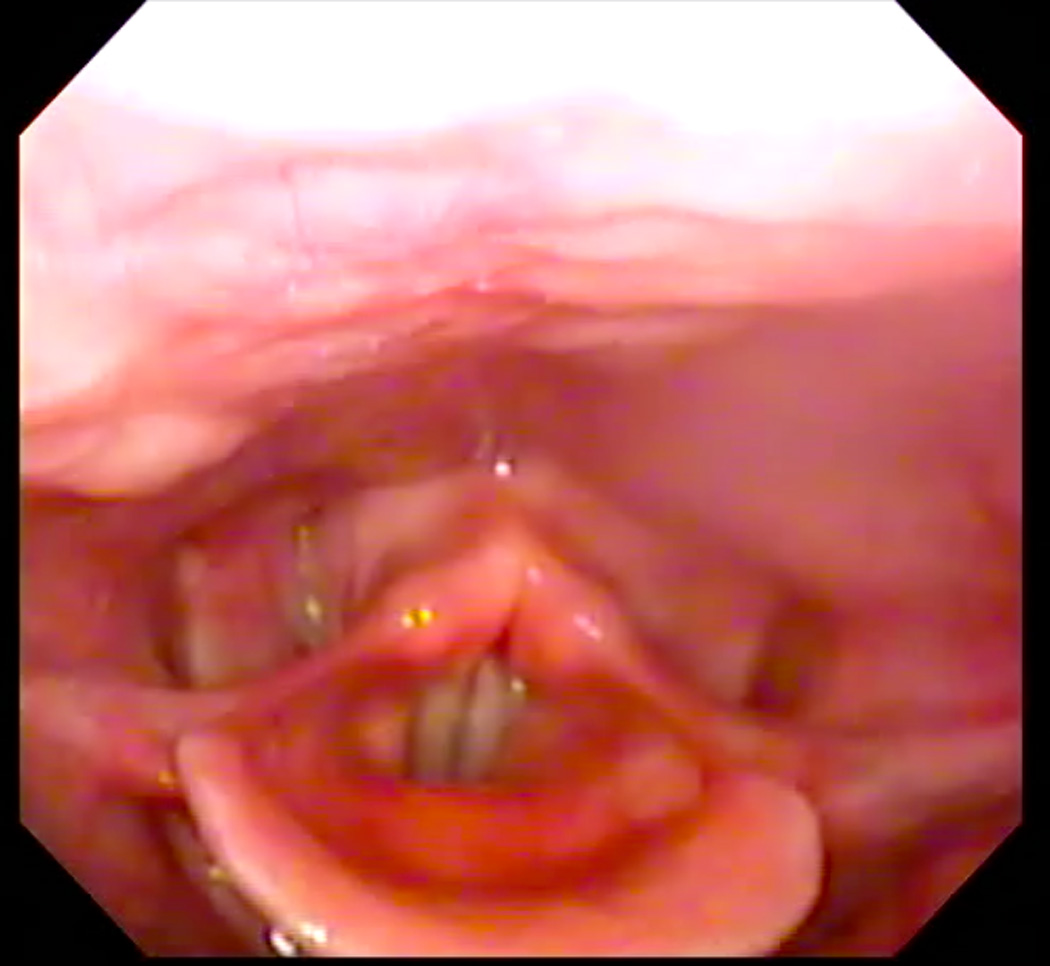

Eleven healthy subjects (six men, five women) age 22–30 years (mean age = 25) participated in this study under a research protocol approved by the Boston Medical Campus Institutional Review Board. Each subject first participated in a laryngoscopic exam and then two-planar dynamic MRI. Subjects were first taught how to produce the /i/ sound starting at their modal pitch, gradually elevating to their highest pitch, and then exerting effort once their highest pitch was attained to produce a forceful “ee” sound, as described by Bastian (1993). When they were able to perform the task perceptually, they were prepared for the laryngoscopic exam using two sprays of a nasal decongestant (neosyenephrine) and two sprays (0.1 ml) of 4% Lidocaine delivered via an atomizer through one nare. Following this, a flexible laryngoscope with an outer diameter of 3.4 mm was passed through the anesthetized nare. The scope was positioned just above the tip of the epiglottis for viewing the hypopharynx. Subjects were again provided with instructions for performing the EPG during the exam. One to three attempts were needed to achieve an acceptable EPG, as judged endoscopically as well as perceptually (see Figure 1, Panels A and B). Each subject completed the exam first in seated and then supine position in order to emulate the required posture for the MRI.

Figure 1.

A: Endoscopic image of hypopharynx at rest. B: Endoscopic image of effortful pitch glide (EPG) illustrating medialization of pharyngeal walls.